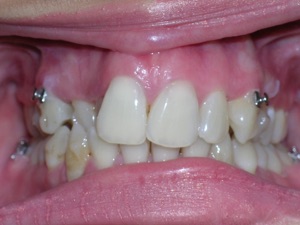

Now for the final results.

Needless to say, we were both quite happy with the outcome. Using elastics we were able to push back the back teeth and create space for the two teeth stuck behind.